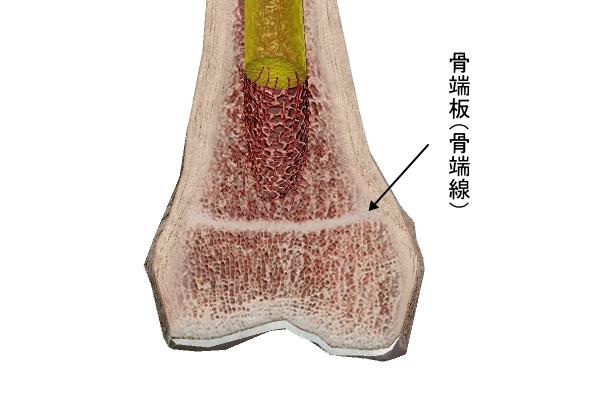

軟骨性関節(軟骨性連結)

硝子軟骨結合と線維軟骨結合の2種がある。

硝子軟骨結合の多くは、軟骨部分が加齢とともに骨化して骨結合になります。

例えば、骨幹と骨端の間にある骨幹板や第一肋骨と胸骨柄を繋ぐ硝子軟骨がそれに当たります。

どちらも骨の成長が止まる10代後半~20代前半には骨化します。